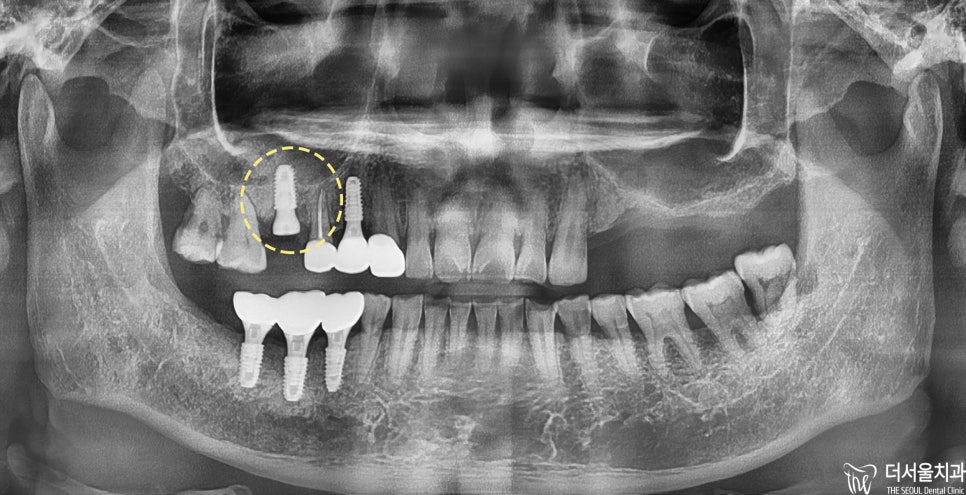

먼저

위턱부터 살펴보면

왼쪽/오른쪽 할 것 없이 치아를 상실했는데

더군다나

치료를 받다가 중단했는지

보철을 씌우지 않은 채로 방치된 모습을 보였습니다.

아래턱을 살펴보면

오른쪽 부위를 상실하였으며

골폭이 줄어든 것을 확인할 수 있었습니다.

오랫동안 치료받지 않고

방치한 만큼

구강 상태가 좋지 못했습니다.

파노라마 촬영 결과

아래와 같은 사실을 알 수 있었습니다.

#16번: 심한 뿌리 끝 염증

#25번: 신경치료 중단 및 골 파괴

#40번대: 치아 상실에 따른 골 흡수